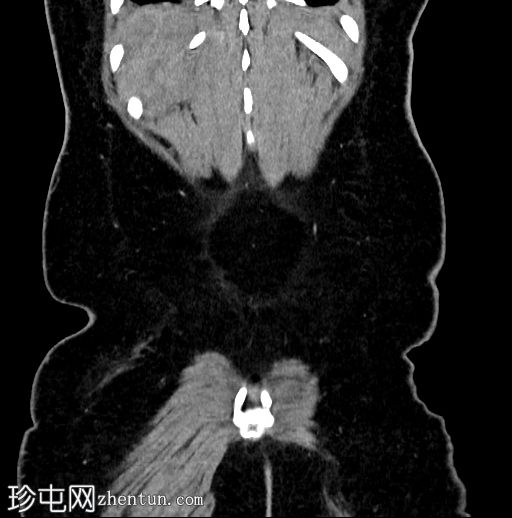

冠状位

2.jpg

右肾周间隙可见高密度影(HU=65),经右侧结肠旁沟延伸至肾盂。

右肾上极区可见一较大、边界清晰、以脂肪密度为主、伴有实性强化成分的病灶,延伸至肾盂。

该病灶延伸至肾盂区域并推移肾盏;但未见侵犯或肾积水。

符合血管平滑肌脂肪瘤破裂的特征。